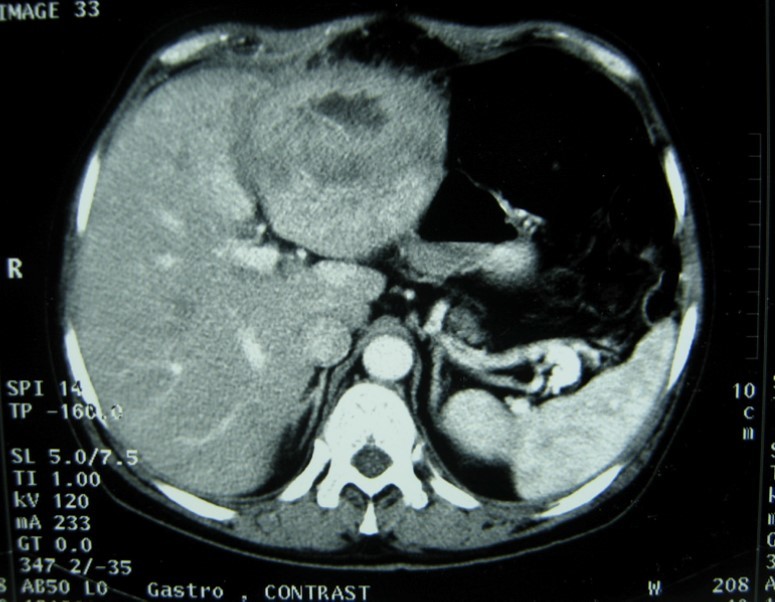

A 17-year-old young man admitted to our department with the complaint of abdominal pain localized in the left upper quadrant for the last 3 months. His physical examination revealed a splenomegaly. Immunoblot assay for Echinococcus was positive. His laboratory tests showed normal results of the serum and urine examinations, No eosinophilia was found. Chest X-ray revealed no pathological signs. An abdominal ultrasonography showed a 20 cm multivesicular cystic mass of spleen (figure 1). Contrast enhanced CT scans detected a huge single 20×16×18cm cystic mass located in the spleen. It had well-defined borders and contained multiple, round, daughter cysts in the periphery of the lesion with calcification (Figure 2, Figure 3, Figure 4). The patient underwent a laparotomy. A large splenic cystic mass was identified, attached to diaphragm, and tail of the pancreas (figure 5). The abdomen was packed with 10% hypertonic saline soaked pads in order to protect peritoneal soilage. A partial cystectomy without splenectomy was performed. Histologic examination of the specimen resection showed an echinococcal organism residing within the hydatid cyst . The patient was discharged after 4 postoperative days. 600 mg per a day of Albendazole therapy was instaured postoperatively and continued for 6 months. Two years after surgery the patient is well with disease free.

Figure 2.CT showing a huge single 20×16×18cm cystic mass located in the spleen

CT showing a huge single 20×16×18cm cystic mass located in the spleen